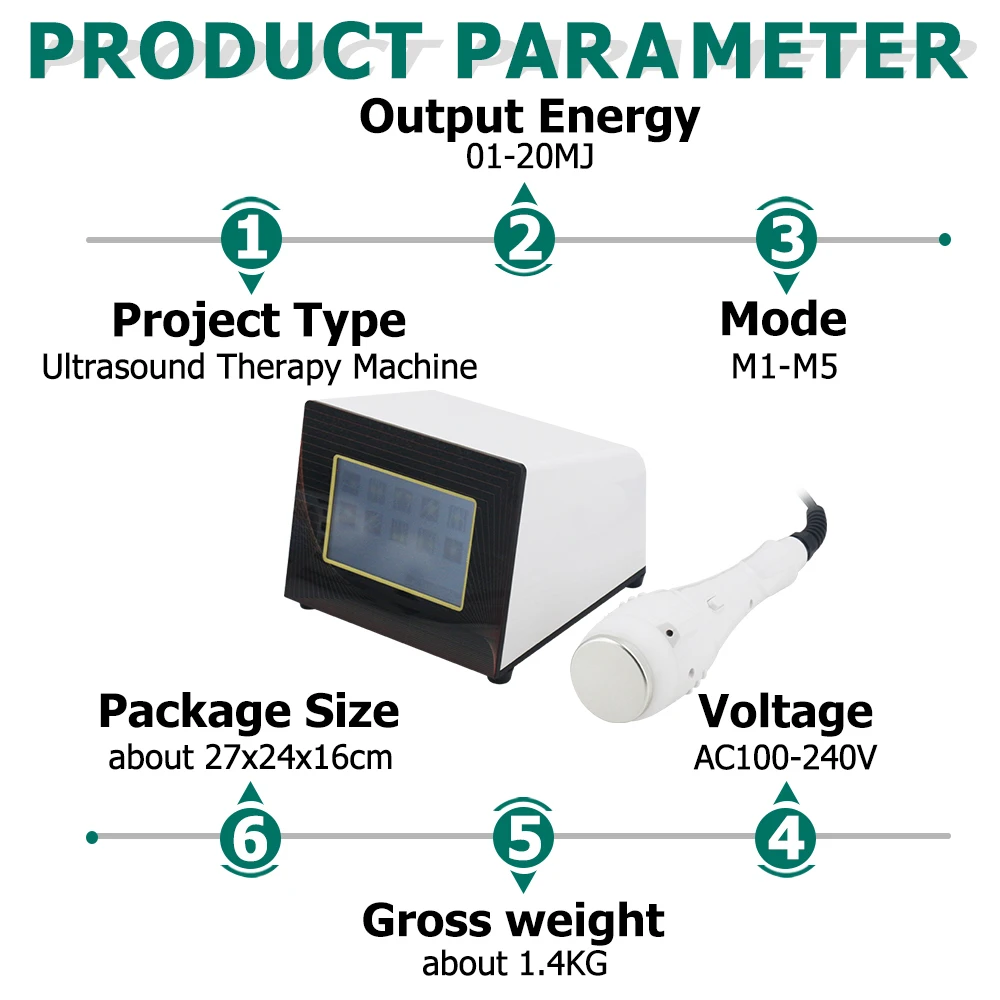

Linear Probe Parameters

-Scanning mode: Electronic array

-Display mode: B, B/M

-Probe element: 80

-Channel of RF circuit board: 16

-Frequency: 7.5MHz/10MH

-Scan depth: 20/40/60/100mm

-Head width: 40mm

-Image Adjust: BGain, TGC, DYN, Focus, Depth, Harmonic, Denoise, Color Gain, Steer, PRF

-Cineplay: auto and manual, frames can set as 100/200/500/1000

-Puncture assist function: the function of in-plane puncture guide line, out-of-plane puncture guide line, automatic blood vessel measurement.

-Measure: Length, Area, Angle, heart rate, Obstetrics

-Image save: jpg, avi and DICOM format

-Image frame rate: 18 frames / second

-Battery working time: 3~5 hours(according to different probe and whether keep scan)

-Battery charge: by USB charge or wireless charge, take 2 hours

-Dimension: 156×60×20mm

-Weight: 220g~250g

-Wifi type: 802.11g/20MHz/5G/450Mbps

-Working system: Apple iOS and Android, Windows 10 system